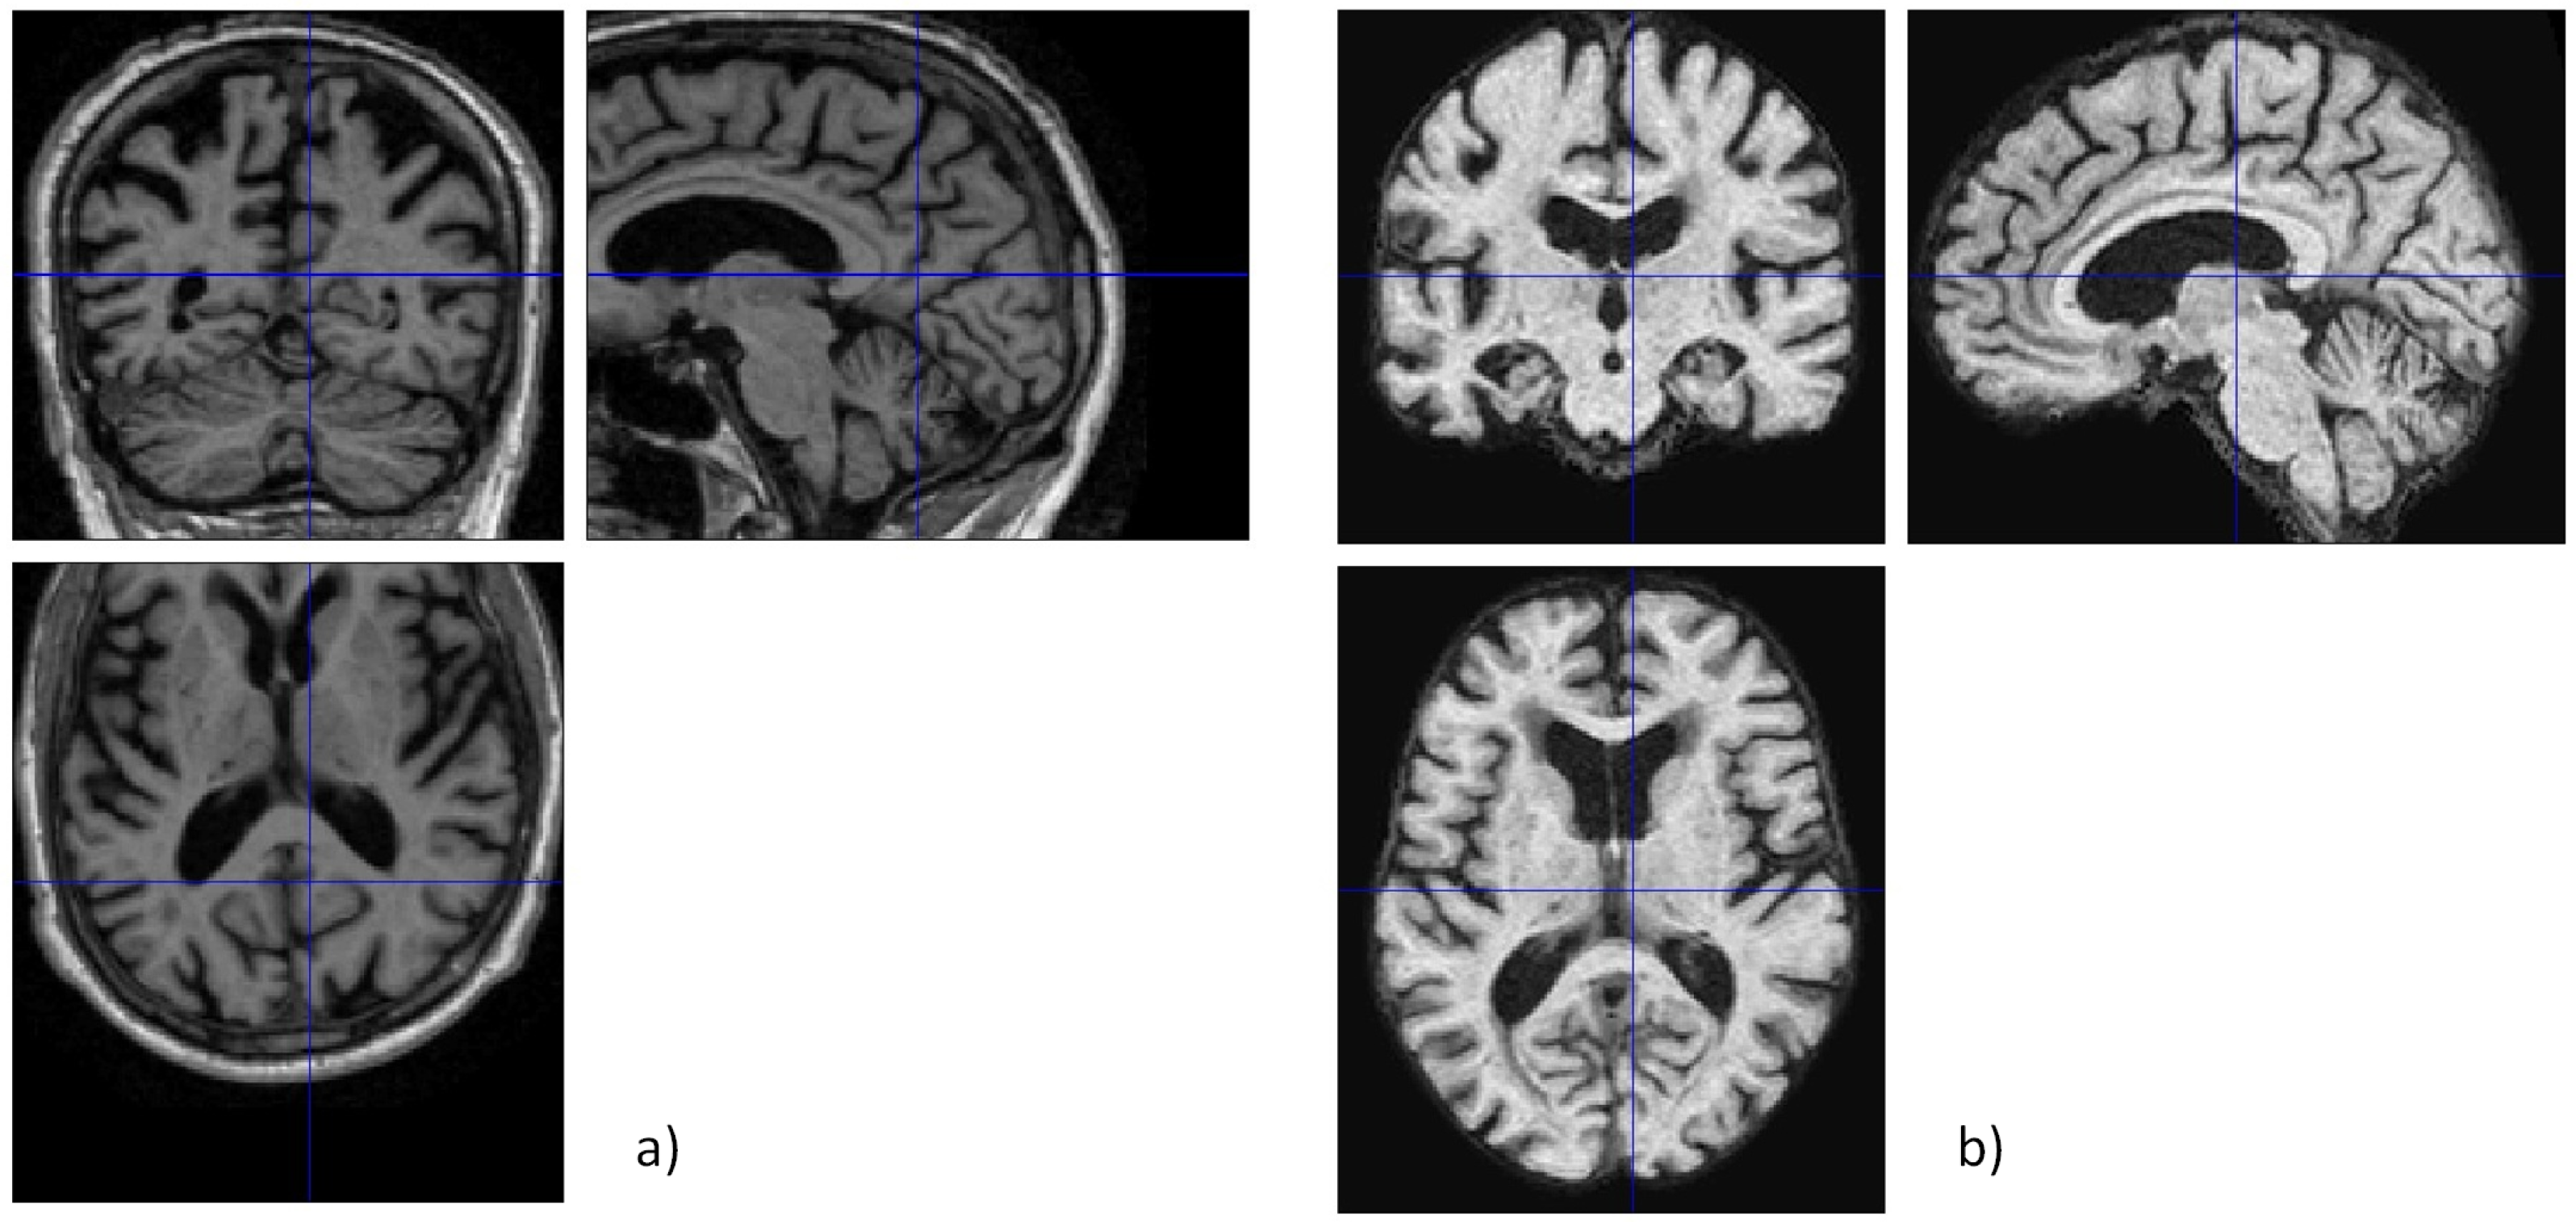

2.2. Image Pre-Processing

2.2.2. Skull Stripping

2.2.3. Slicing and Final Pre-Processing Steps